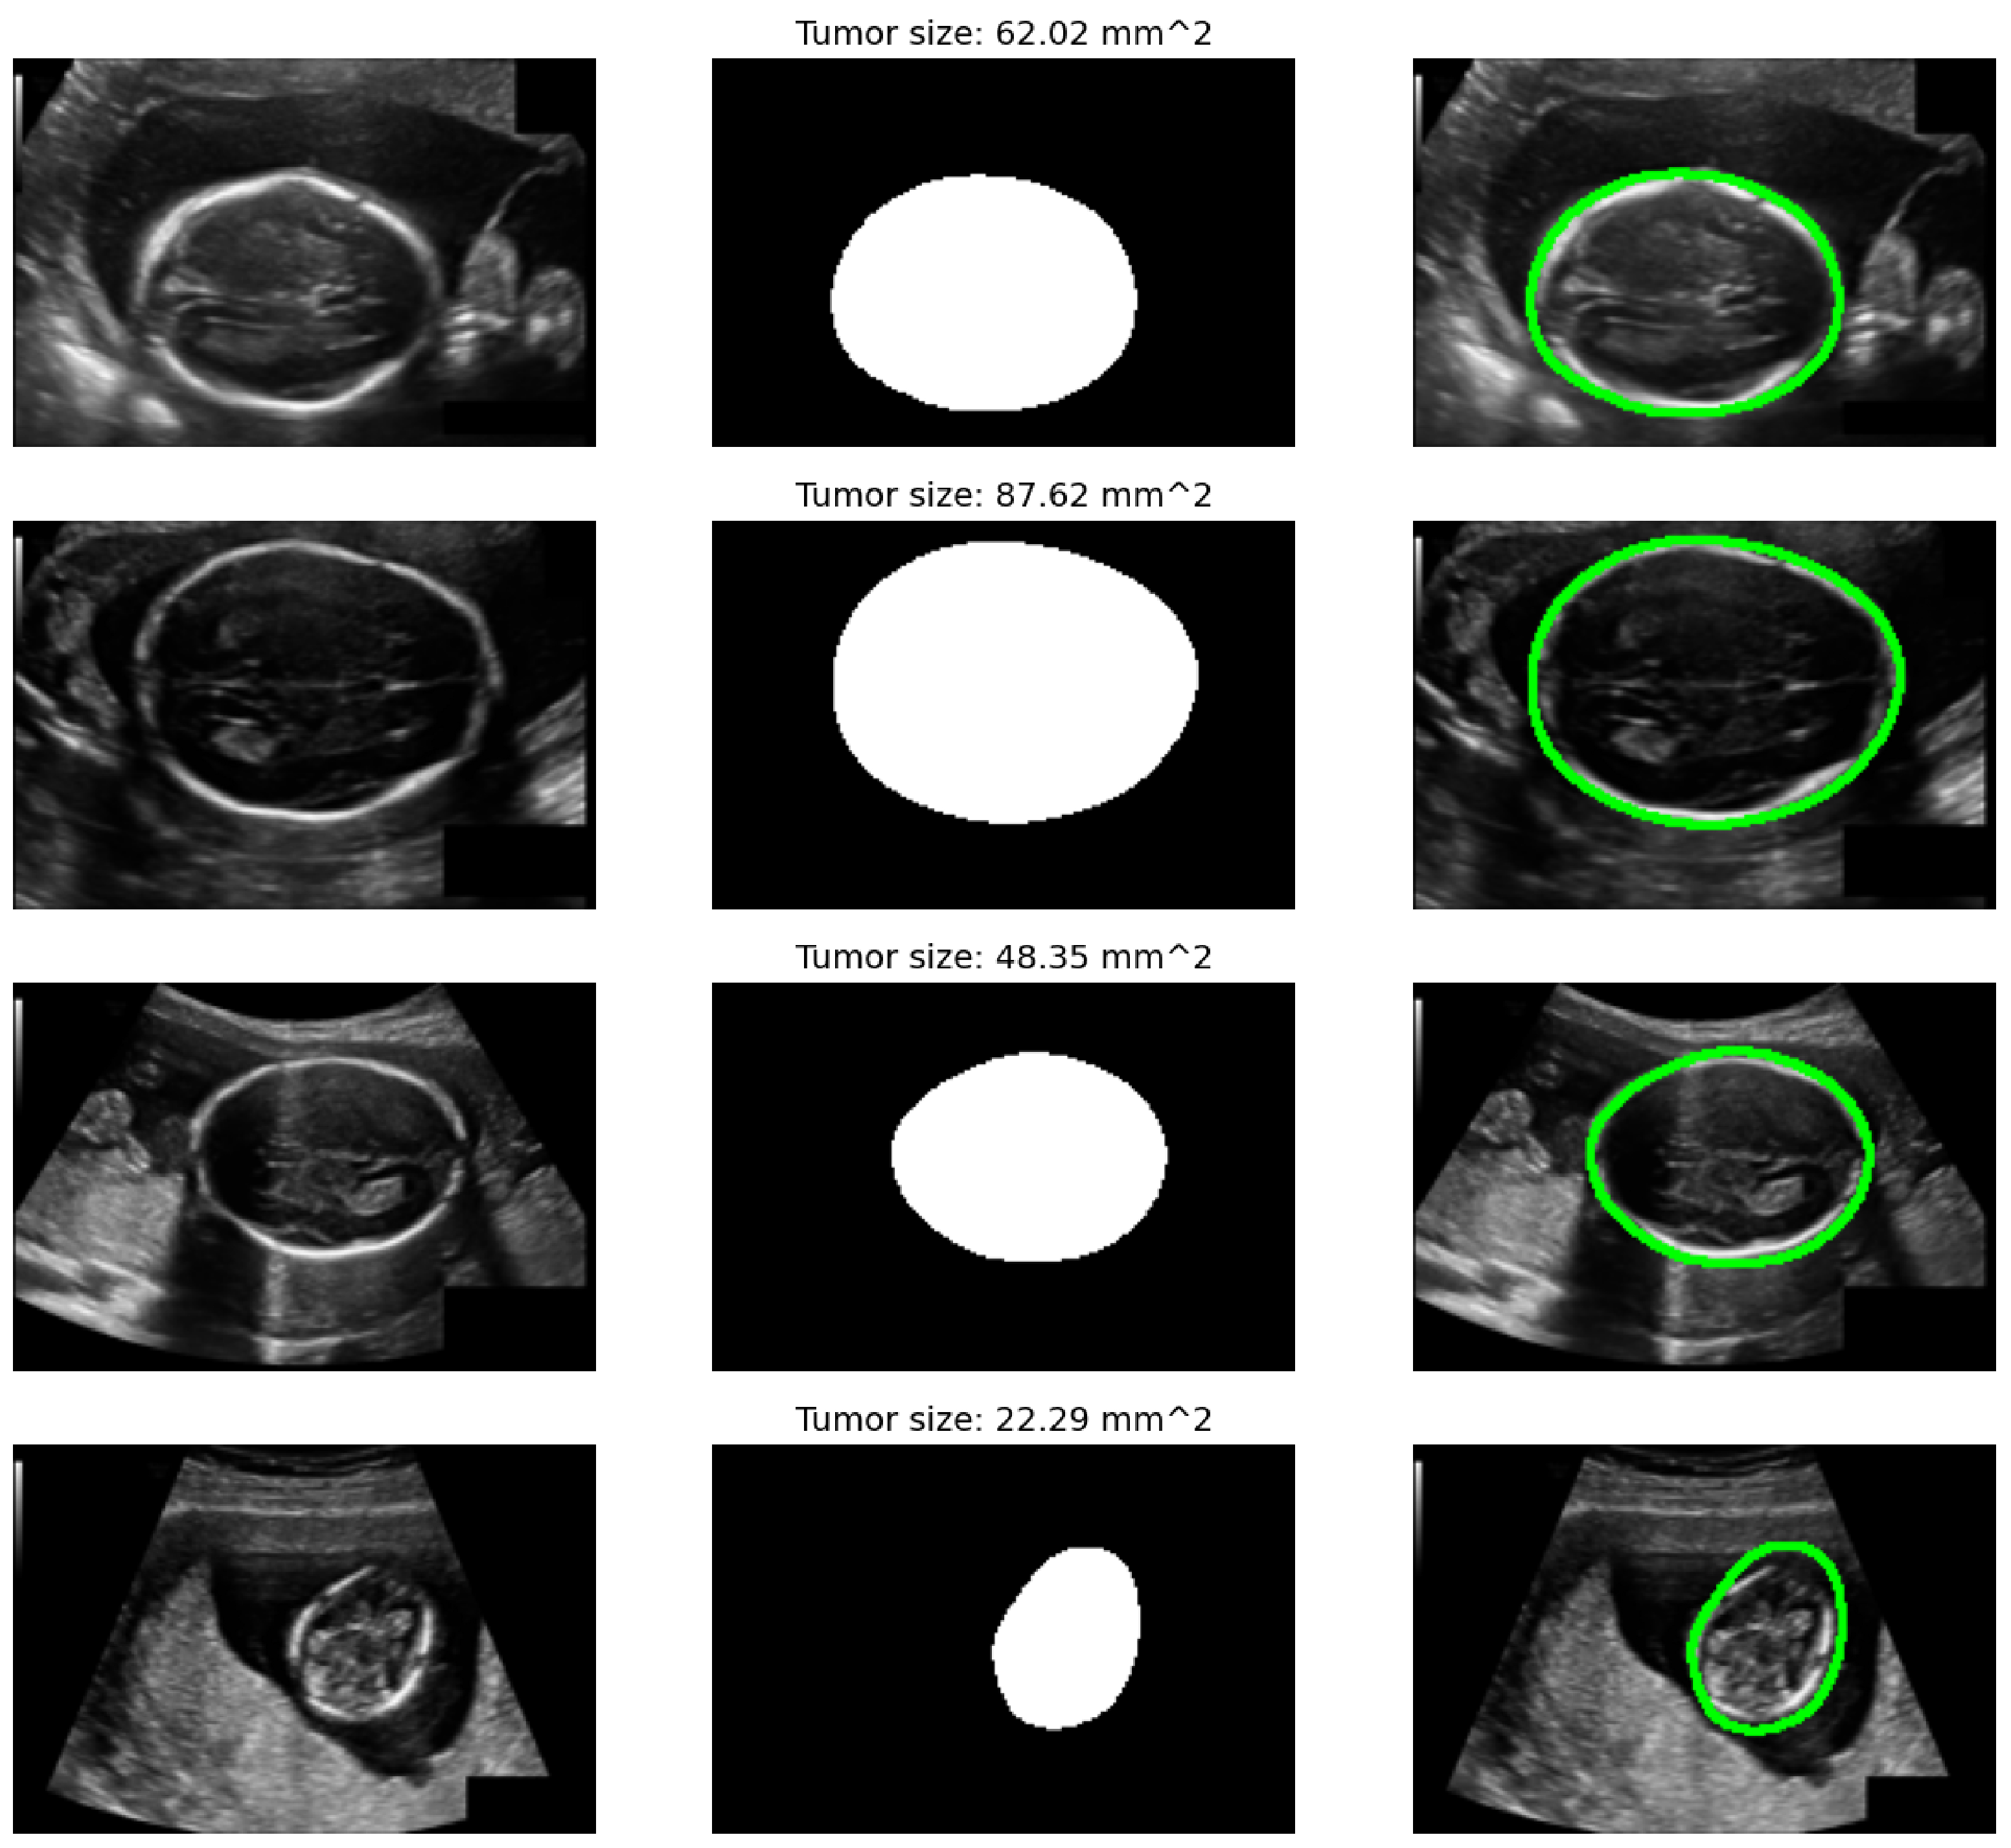

4.1. Datasets and Experimental Setup

| Model | Dice (%) | IoU (%) | HD95 (mm) | MAE (mm) | RMSE (mm) | Corr | |

| HC18 | UNet baseline | 93.8 ± 0.4 | 88.3 ± 0.5 | 2.40 ± 0.18 | 2.90 ± 0.20 | 3.80 ± 0.25 | 0.962 ± 0.006 |

| ViT-only head | 94.6 ± 0.3 | 89.6 ± 0.4 | 2.10 ± 0.16 | 2.70 ± 0.18 | 3.60 ± 0.22 | 0.968 ± 0.005 | |

| SSM-only head | 94.8 ± 0.3 | 90.0 ± 0.4 | 2.00 ± 0.15 | 2.60 ± 0.17 | 3.50 ± 0.20 | 0.970 ± 0.005 | |

| Hybrid (Ours) | 95.7 ± 0.3 | 91.7 ± 0.3 | 1.70 ± 0.14 | 2.30 ± 0.16 | 3.20 ± 0.19 | 0.978 ± 0.004 |